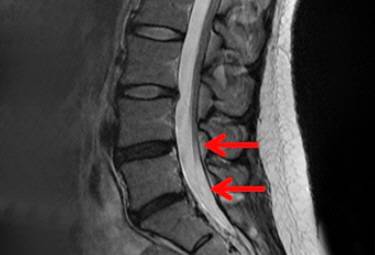

디스크 내장증의 경우 일반 X-RAY나 CT로 발견이 어렵고, MRI 검사를 통해 확인할 수 있어 진단이 늦어지는 경우가 많다.

MRI 검사 시 정상 허리 디스크는 흰색으로 보이지만, 디스크 내장증이 발병한 허리 디스크는 검은색(블랙 디스크)으로 관찰된다.